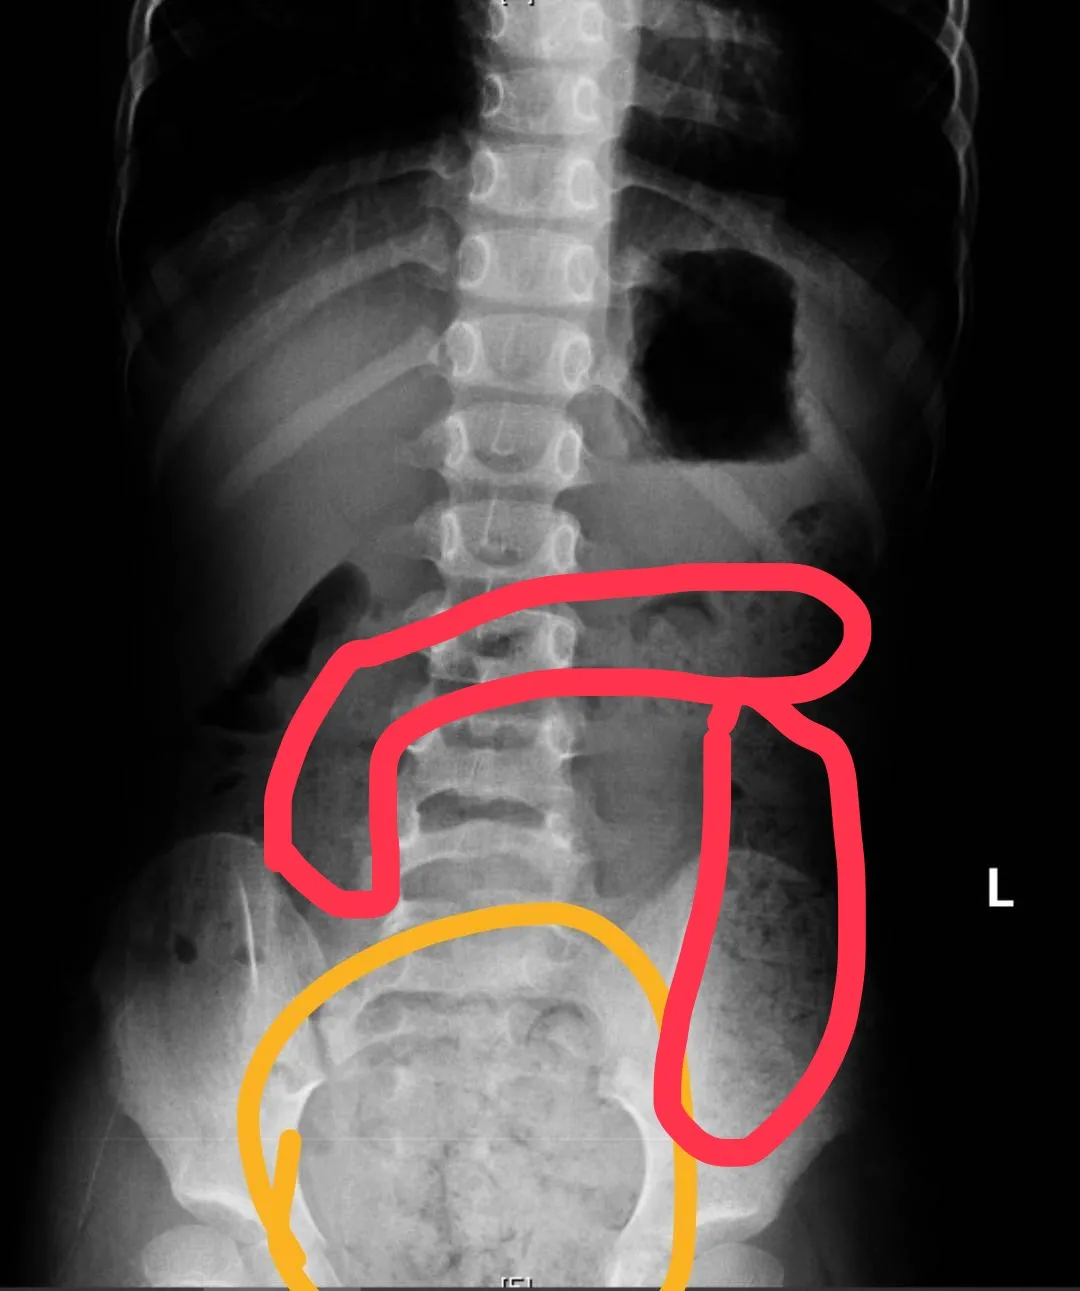

11歲男生X光片,畫圈部分為積糞。翻攝畫面